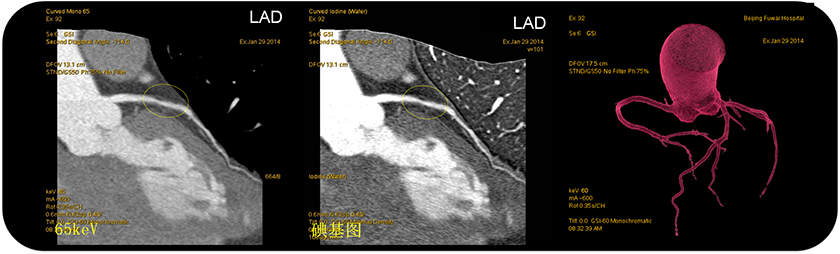

病例展示:曲面重建、VR-Tree、能谱曲线图像

2条蓝色曲线:斑块含脂性成分, 1条绿色曲线:纤维斑块

点评:冠脉能谱CT可以展示不同物质的能谱曲线,对成分的敏感性更高。利用能谱曲线可以精确地分析斑块性质,尤其对于冠脉易损斑块的探测,有效预防急性心梗,对急性冠脉综合征等具有重要价值